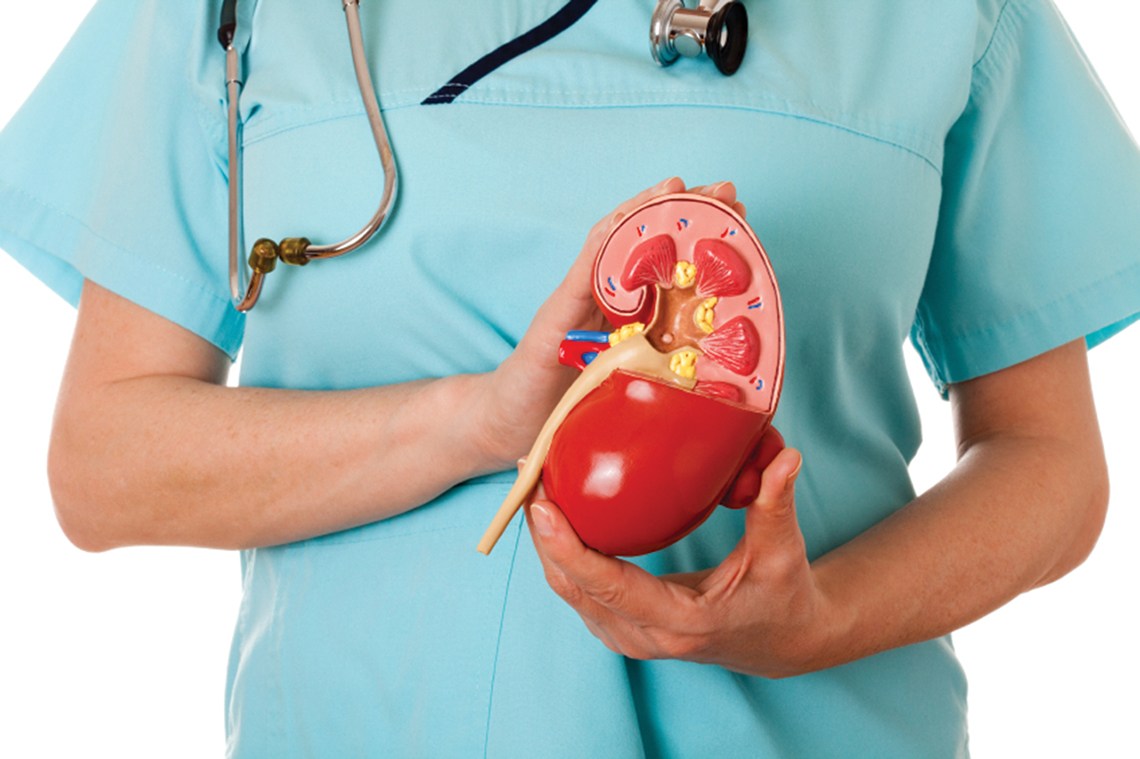

Περιτοναϊκή κάθαρση

Η περιτοναϊκή κάθαρση (ΠΚ) καθαρίζει το αίμα σας και απομακρύνει τα πλεονάζοντα υγρά χρησιμοποιώντας ένα από τα φυσιολογικά φίλτρα του οργανισμού σας, την περιτοναϊκή μεμβράνη.